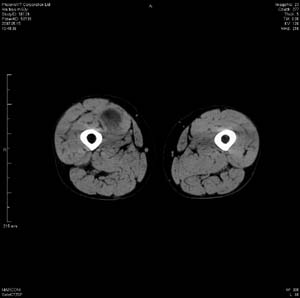

男 63岁 右大腿无痛性肿块11年,x片右大腿软组织肿块影,余无明显异常.ct值-13__239hu

右大腿股内侧股与收肌间隙间多发囊实性占位,界清.内示斑点状钙化.局部骨质无异常.肌肉推压移位表现.

考虑肌间隙病变.可有1,神经来源肿瘤.2,血管来源病变.3,淋巴来源肿瘤.4,脂肪来源肿瘤.5,滑膜来源肿瘤.结合病史只能考虑良性占位.建议增强或mri进一步分析.

同意,病史较长,病变周围分界清晰,考虑良性病变。病灶内有多发斑点状钙化,沿肌间隙生长,血管瘤或淋巴管瘤首先考虑。